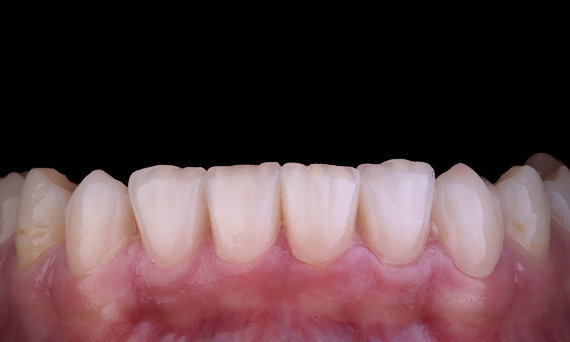

It is quite common to observe cracks and fractures associated with amalgam restorations, particularly as they increase in size as they are ‘unbonded’ restorations. Many of these teeth are structurally compromised and an adhesive, biomimetic approach is the ideal method of restoring these teeth. As a part of a more comprehensive treatment plan, this quadrant was planned to have two indirect ceramic onlays. The first and second molars were restored in a single visit using CEREC Tessera, an advanced lithium disilicate.

Dr Yo-Han Choi, Sydney, Australia